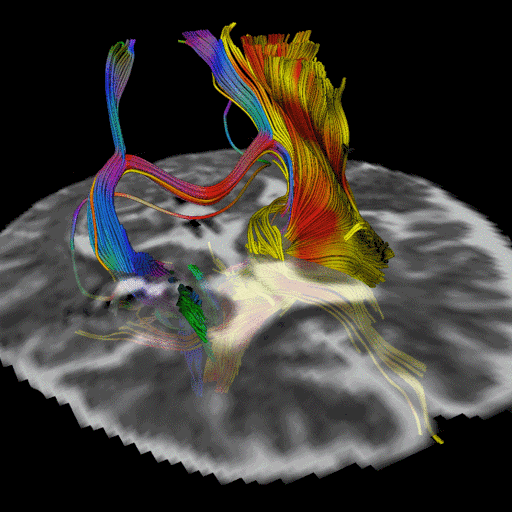

(Og PFP

)